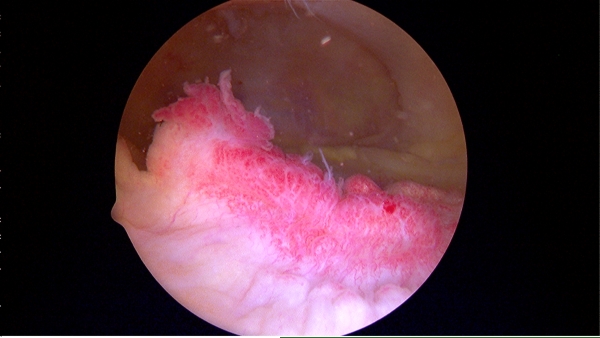

Артроскопия — это метод исследования внутренних структур коленного сустава с использованием артроскопа. Этот инструмент предоставляет детализированные изображения тканей мениска, на основе которых врач может установить точный диагноз и назначить адекватное лечение.

Важно отметить, что на основе артроскопии был разработан современный метод терапии воспалительных процессов. Он позволяет вводить медикаменты непосредственно в пораженные ткани и проводить операции по удалению поврежденных участков мениска.